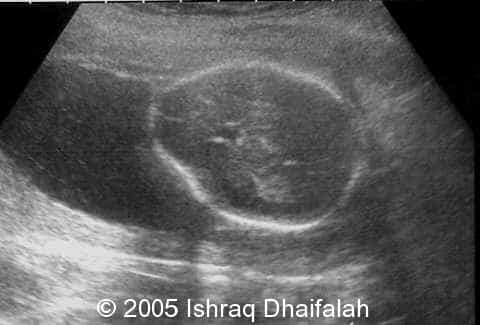

Abnormal shape of the head of fetus B:

image3